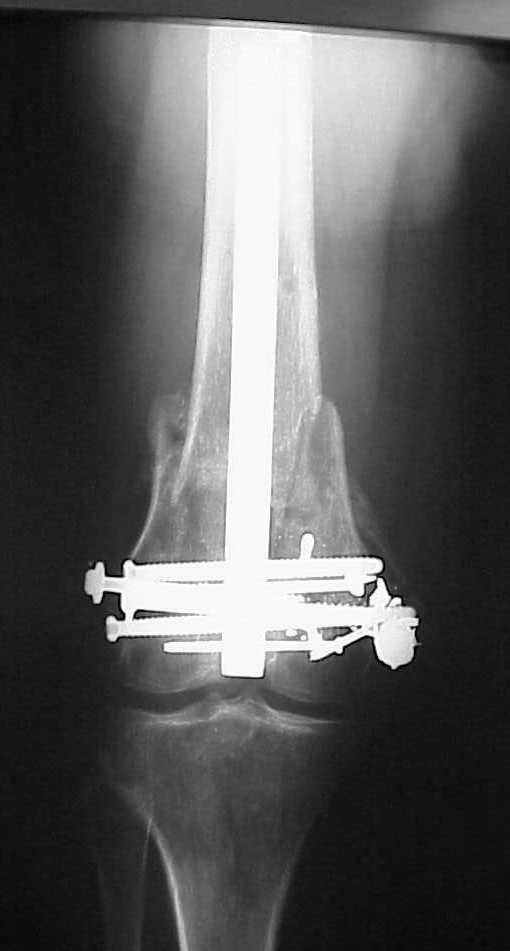

A CT and knee xrays would help identify lateral condyle comminution and/or a "hoffa fragment" of the posterior condyle. I am concerned that the lateral cortex is not sufficient to give purchase for a retrograde IMN. blocking screws could improve this as a possibility. A long blade or LISS if avaible would be my secondary choices. Good luck. Any chance you can get these cases transferred earlier when it

Use 6.5 mm cannulated screws if you have and

place one anterior to where IMN will go if anterior cortex if insufficient and AP screws on either side of the IMN out of the trochlea to provide some additional varus/valgus stability. I worry about the leg going into valgus w/the lack of lateral cortex.

See attached case that was done several years ago before LISS. He had comminuted trochlea and anterior blocking screws were used to prevent anterior IMN cut-out.